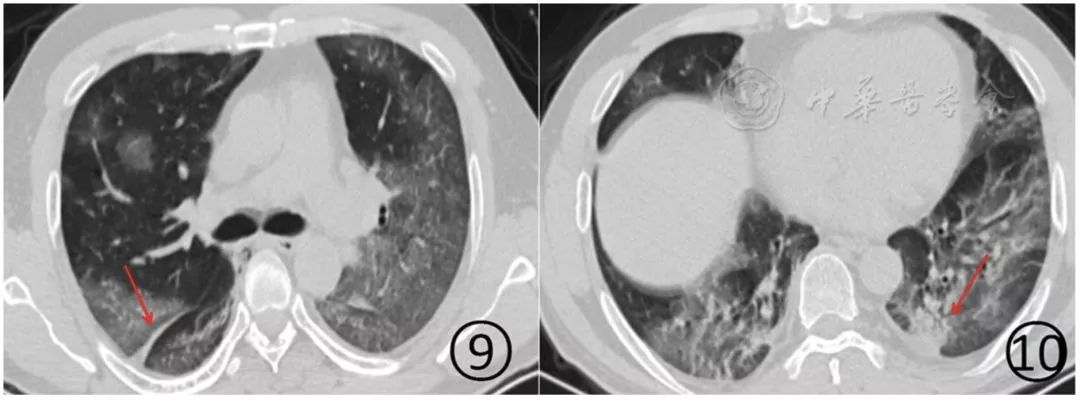

表现为单发或多发的局限性磨玻璃阴影、结节(图5,图6),非常淡薄的小斑片磨玻璃阴影(图7,图8)或者大片磨玻璃阴影(图9,图10),多数磨玻璃阴影边缘不清,部分边缘清晰。

病变多分布于中、下叶,多位于胸膜下(图5,图6)或叶间裂下(图7,图8),或者沿支气管血管束分布。

图9,10 男,50岁。CT平扫肺窗显示两肺大片磨玻璃阴影和斑片状磨玻璃阴影,多分布于肺的中外带、胸膜下。右侧斜裂有增厚(图9↑),左下后段胸膜下有实变(图10↑)